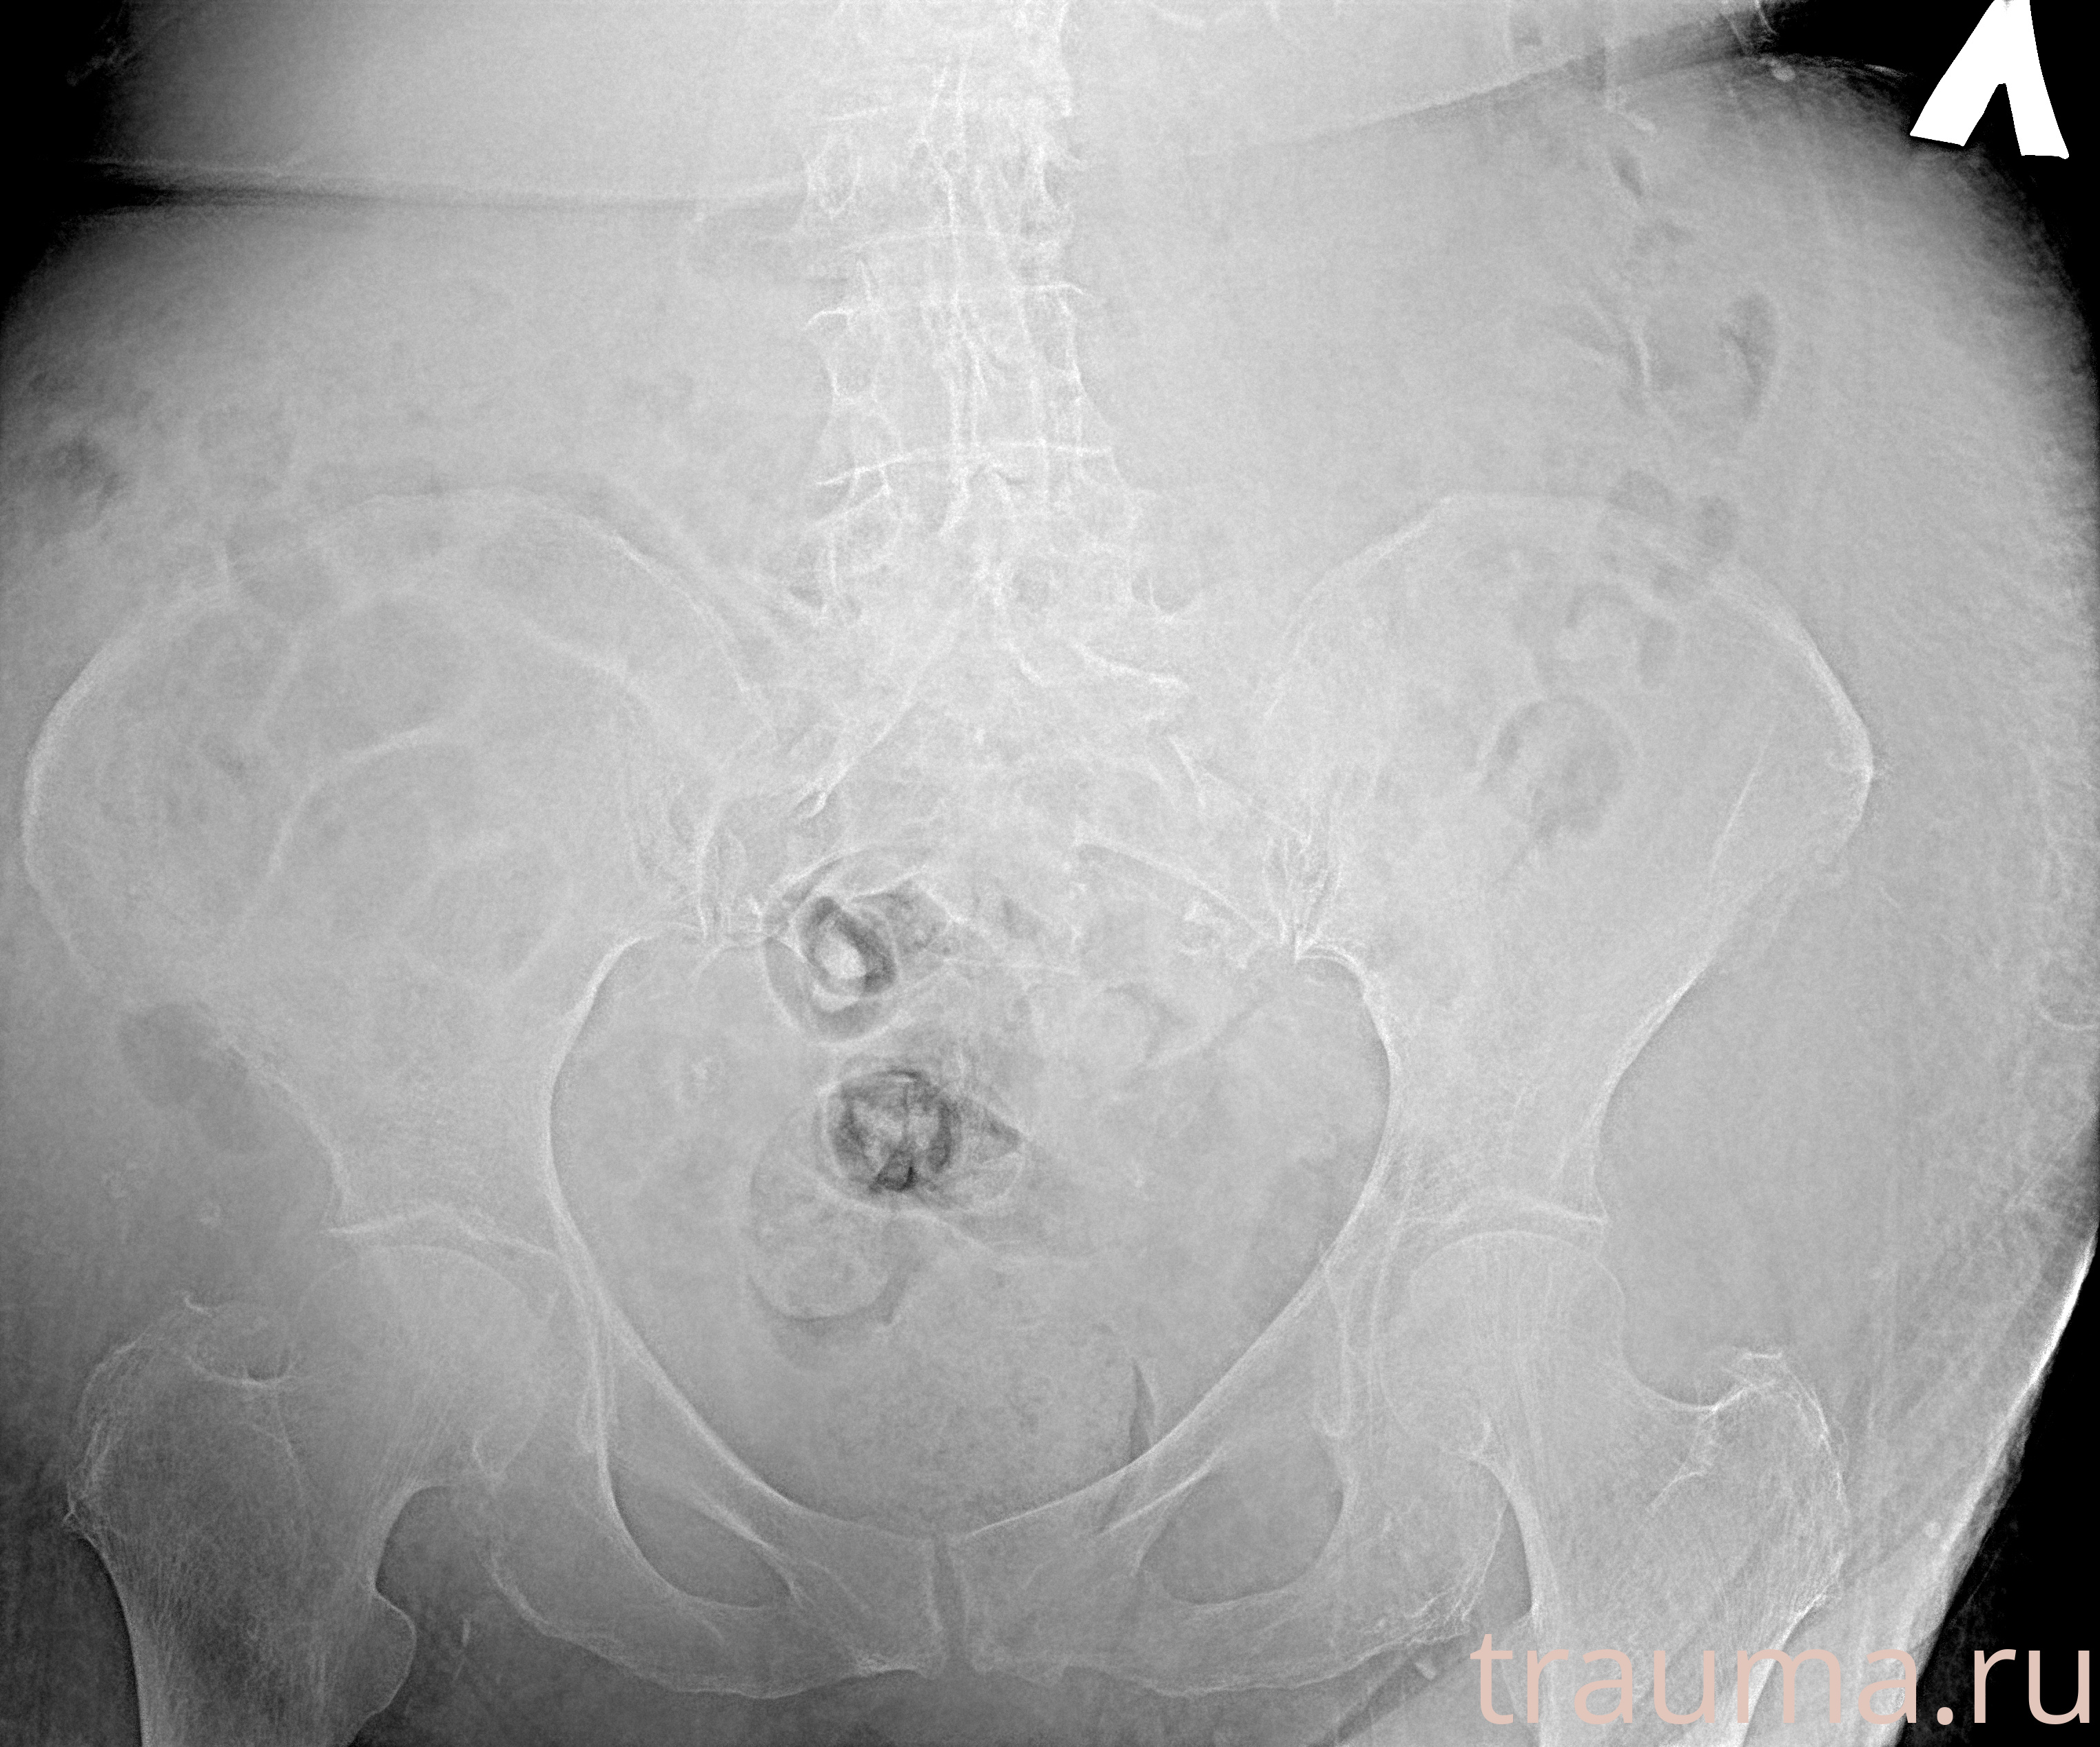

Рентгенограммы

Рентген на дому: по вашему адресу приезжает врач-рентгенолог, травматолог-ортопед с мобильным рентгеновским аппаратом, проводит диагностику травмы или заболевания, делает необходимые рентгенограммы, дает рекомендации по дальнейшему лечению. Получить качественные снимки в домашних условиях возможно благодаря уникальной методике, разработанной МосРентген Центром для института  Склифосовского